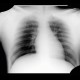

Both CT sections and radiographs show a foreign body of metallic density with metallic artifacts on CT which is lodged in the chest wall anteriorly to the sternal end of the left collar bone.